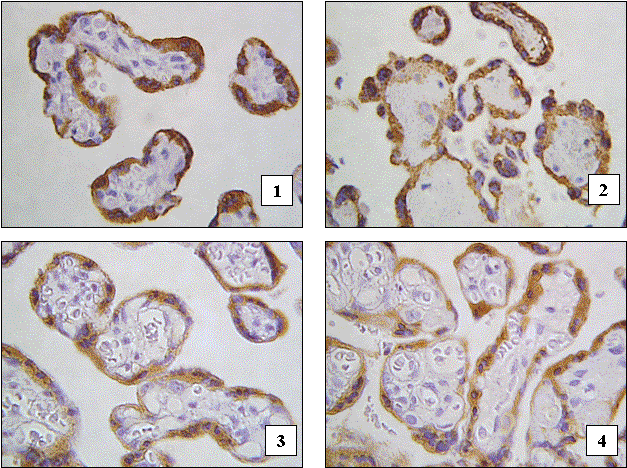

Вказані закономірності щодо концентрації плацентарного лактогену у синцитіотрофобласті хоріальних ворсин проілюстровані за допомогою цифрових мікрофотографій на рисунку 1.

Рис. 1. Різна концентрація плацентарного лактогену у синцитіотрофобласті хоріальних ворсин при плацентах звичайної форми та екстрахоріальних плацентах в аспекті хронічної плацентарної недостатності:

1 - плацента звичайної форми з фізіологічним перебігом вагітності;

2 - екстрахоріальна плацента з фізіологічним перебігом вагітності;

3 - плацента звичайної форми з клінічними проявами хронічної плацентарної недостатності;

4 - екстрахоріальна плацента з клінічними проявами хронічної плацентарної недостатності.

Імуногісто­хімічна методика з первин­ними антитілами проти плацентарного лактогену та візуалізацією первинних антитіл стрептавідин-біотиновим методом з використанням діамінобензи­дину. Дофарбовування клітинних ядер гемалауном Майера. Об.40х, Ок.10 х.